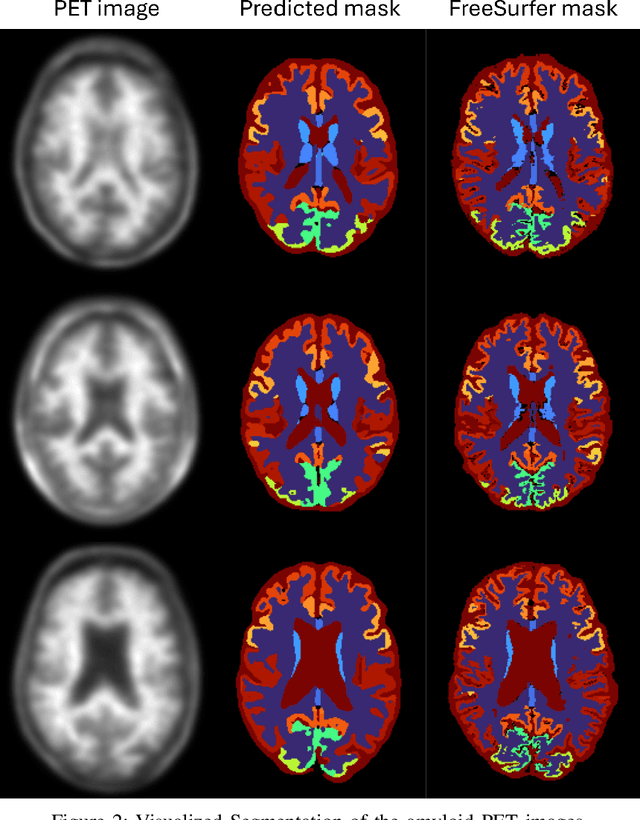

Abstract:This study proposes a deep learning-based framework for automated segmentation of brain regions and classification of amyloid positivity using positron emission tomography (PET) images alone, without the need for structural MRI or CT. A 3D U-Net architecture with four layers of depth was trained and validated on a dataset of 200 F18-florbetapir amyloid-PET scans, with an 130/20/50 train/validation/test split. Segmentation performance was evaluated using Dice similarity coefficients across 30 brain regions, with scores ranging from 0.45 to 0.88, demonstrating high anatomical accuracy, particularly in subcortical structures. Quantitative fidelity of PET uptake within clinically relevant regions. Precuneus, prefrontal cortex, gyrus rectus, and lateral temporal cortex was assessed using normalized root mean square error, achieving values as low as 0.0011. Furthermore, the model achieved a classification accuracy of 0.98 for amyloid positivity based on regional uptake quantification, with an area under the ROC curve (AUC) of 0.99. These results highlight the model's potential for integration into PET only diagnostic pipelines, particularly in settings where structural imaging is not available. This approach reduces dependence on coregistration and manual delineation, enabling scalable, reliable, and reproducible analysis in clinical and research applications. Future work will focus on clinical validation and extension to diverse PET tracers including C11 PiB and other F18 labeled compounds.